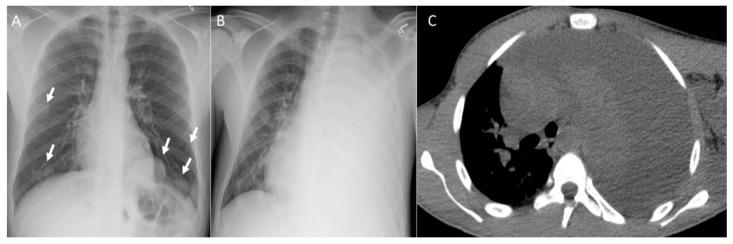

Osteosarcoma, a primary bone malignancy in children and adolescents, frequently metastasizes to the lungs, contributing significantly to morbidity and mortality. At diagnosis, 15-20% of patients present with detectable lung metastases. Chest computed tomography (CT) is vital for the early detection and monitoring of these metastases. Lung involvement typically presents as multiple nodules of varying sizes and can include atypical features such as cavitation, cystic lesions, ground-glass halos, intravascular tumor thrombi, and endobronchial disease. Pleural metastasis often occurs alongside pulmonary disease, and complications like spontaneous pneumothorax may arise. Additional findings may include thoracic lymphadenopathy, cardiac tumor thrombus, and chest wall deposits. Familiarity with these imaging patterns is essential for radiologists to ensure timely diagnosis and effective management. This review highlights the critical role of chest CT in detecting and characterizing osteosarcoma metastasis.

骨肉瘤是儿童和青少年常见的原发性骨恶性肿瘤,常转移至肺部,对发病率和死亡率有显著影响。在诊断时,15%至20%的患者出现可检测到的肺转移。胸部计算机断层扫描(CT)对于这些转移灶的早期检测和监测至关重要。肺部受累通常表现为大小不一的多个结节,可包括一些非典型特征,如空洞形成、囊性病变、磨玻璃晕、血管内肿瘤血栓和支气管内病变。胸膜转移常与肺部疾病同时发生,可能出现自发性气胸等并发症。其他表现可能包括胸内淋巴结肿大、心脏肿瘤血栓和胸壁转移灶。放射科医生熟悉这些影像学表现对于确保及时诊断和有效治疗至关重要。本综述强调了胸部CT在检测和鉴别骨肉瘤转移方面的关键作用。